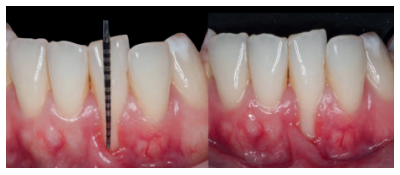

El examen clínico periodontal reveló la presencia de recesión gingival de 5 mm en el diente 31 con una profundidad de sondaje vestibular de 2 mm (perdida de inserción clínica de 7 mm). Presentaba inflamación gingival, además de un frenillo labial inferior insertado en el margen apical de la recesión gingival. El tejido queratinizado faltaba por completo a nivel del diente con recesión (Figura 1). Debido a que el defecto gingival se extendía más allá de la línea mucogingival, así como a la presencia de malposición dentaria, la recesión se categorizó como clase III de Miller6 y RT2 de Cairo7 .

Mujer de 23 años que acudió a nuestra consulta debido a la presencia de múltiples recesiones gingivales desde el diente 32 al 42. La paciente refiere que nota sus dientes más largos, no presenta problemas de hipersensibilidad y había terminado el tratamiento ortodóncico hacía 1 año. La historia médica de la paciente no mostraba datos relevantes. No informó de alergias y no tomaba medicación de ningún tipo. El examen clínico periodontal reveló múltiples recesiones gingivales vestibulares que afectaban a los dientes 32, 31, 41 y 42 (Figura 9), con ausencia de tejido queratinizado apical a las recesiones de los dientes 31 y 32. Tras el estudio radiográfico (Figura 10) se observa pérdida ósea horizontal leve entre los incisivos inferiores (clase III de Miller y RT2 de Cairo).